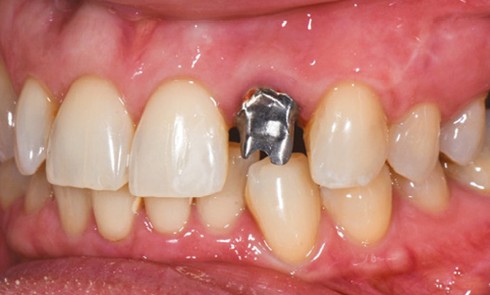

Article réservé à nos abonnés La prothèse fixée implantaire : scellée ou vissée ?

La prothèse scellée Le scellement de restaurations sur des piliers implantaires demeure une solution très intéressante (fig. 1). Cette technique reprend...